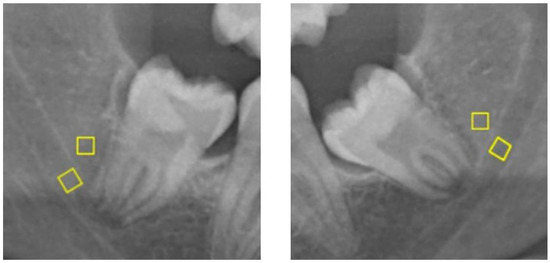

Attempting to Determine the Relationship of Mandibular Third Molars to the Mandibular Canal on Digital Panoramic Radiography; Using CBCT as Gold Standard

by Hilal Isra Erkan, Osman Yalcin, Umut Pamukcu and Kahraman Gungor

(1) Background: It is important to know, radiologically, the relationship of Mandibular third molars (M3) to the mandibular canal to minimize postoperative complications by causing damage to the inferior alveolar vessels and nerve during extraction. This study aimed to evaluate the usability of various image analyses or high-risk radiographic findings in determining the relationship of M3s to the mandibular canal on Digital Panoramic Radiography (DPR). (2) Methods: DPRs of 60 patients with bilateral mandibular M3s in the dental arch, determined one of them to be related to the mandibular canal unilaterally by Cone Beam Computed Tomography (CBCT), were included. The high-risk radiological signs of M3s and Fractal Analysis (FA) and Histogram Analysis (HA) measurements of the trabecular bone around the M3s’ roots were compared. The Independent t-test, Kolmogorov–Smirnov, Mann–Whitney U, and Chi-Square tests were used for statistical analyses. (3) Results: DPR signs, such as radiolucency and bifurcation at the root apex, discontinuity of the mandibular canal cortex, and superimposition of the tooth root and mandibular canal, were observed statistically significantly more frequently for mandibular canal-related M3s (p < 0.05). As an objective image analysis, Lacunarity showed a statistically significant difference between related and unrelated M3s for measurements made inside and outside the mandibular canal (p < 0.05). (4) Conclusions: This study demonstrated that the discontinuity of the mandibular canal cortex and Lacunarity measured on DPR could help determine the relationship of the mandibular M3s to the mandibular canal. Full article